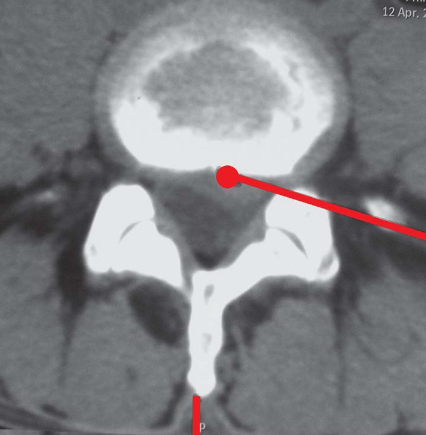

靶点:突出物的基底部(图4)。

图4靶点CT轴位片:L4/5突出物的基底部

1.穿刺时,勺状针头位置受上关节突尖的干扰稍靠头端,要注意出口神经根的保护(图11);应用双针技术是合适的(图13)。